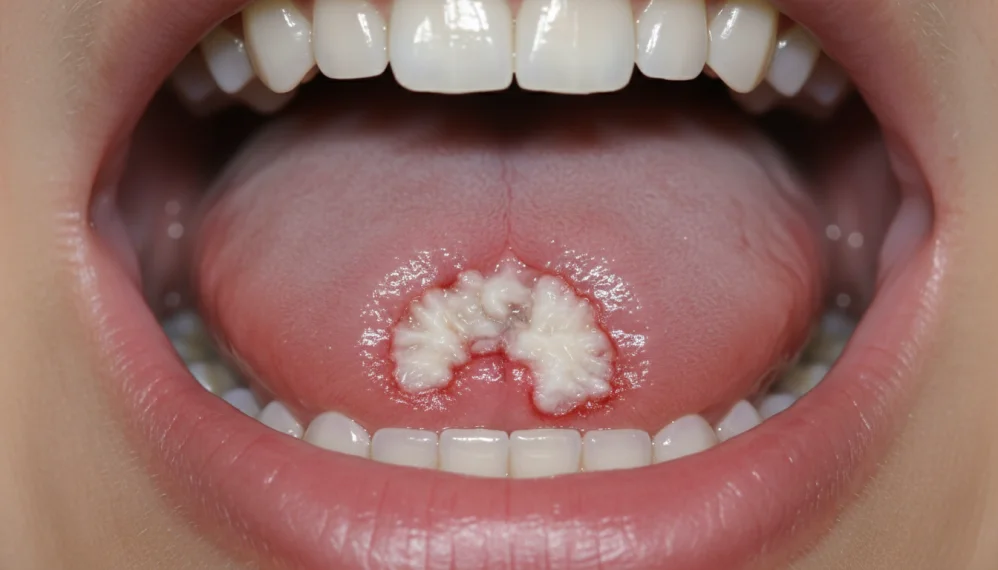

Cancerul de limba este mai frecvent intalnit la barbati, cu un debut insidios, sub forma de ulceratie, nodul sau o proliferare conopidiforma. Apare senzatia de corp strain, durere la inghitire, iar starea generala se altereaza datorita dificultatilor in alimentatie.

Cancerul planseu bucal poate sa apara sub forma de ulceratie putand fi confundat cu o leziune provocate de proteza.